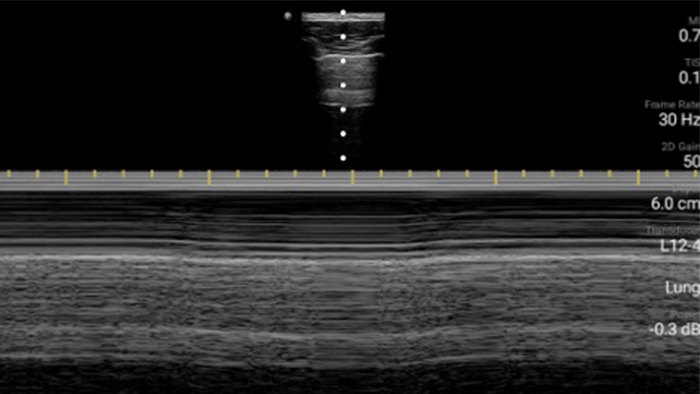

Ultrasound exams can improve your ability to identify and successfully treat skin abscesses.

Lumify L12-4 broadband linear array transducer

From revealing the subtle details of an image to uncovering enriched tissue definition from multiple angles, Lumify can help you make real-time decisions with more confidence from assessment through recovery.